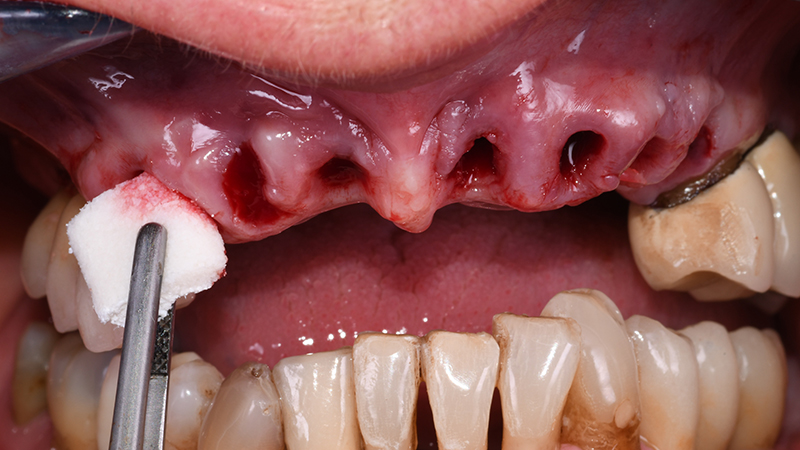

In seguito ad anestesia per infiltrazione mediante articaina cloridrato + vasocostrittore (adrenalina 1:100.000), sono state eseguite le estrazioni degli elementi interessati (Fig. 6)

Dopo aver verificato la posizione della dima chirurgica sul modello digitale stampato, quest’ultima è stata posizionata in bocca tramite il supporto dentale dei settori latero-posteriori ed un pin di fissaggio è stato applicato (Anchor Pin Kit, Megagen, Daegu, Corea del Sud) (Figs. 7, 8, 9)

Alveoli post-estrattivi prima di applicare R2Guide

Fig. 6 - Alveoli post-estrattivi prima di applicare R2Guide®